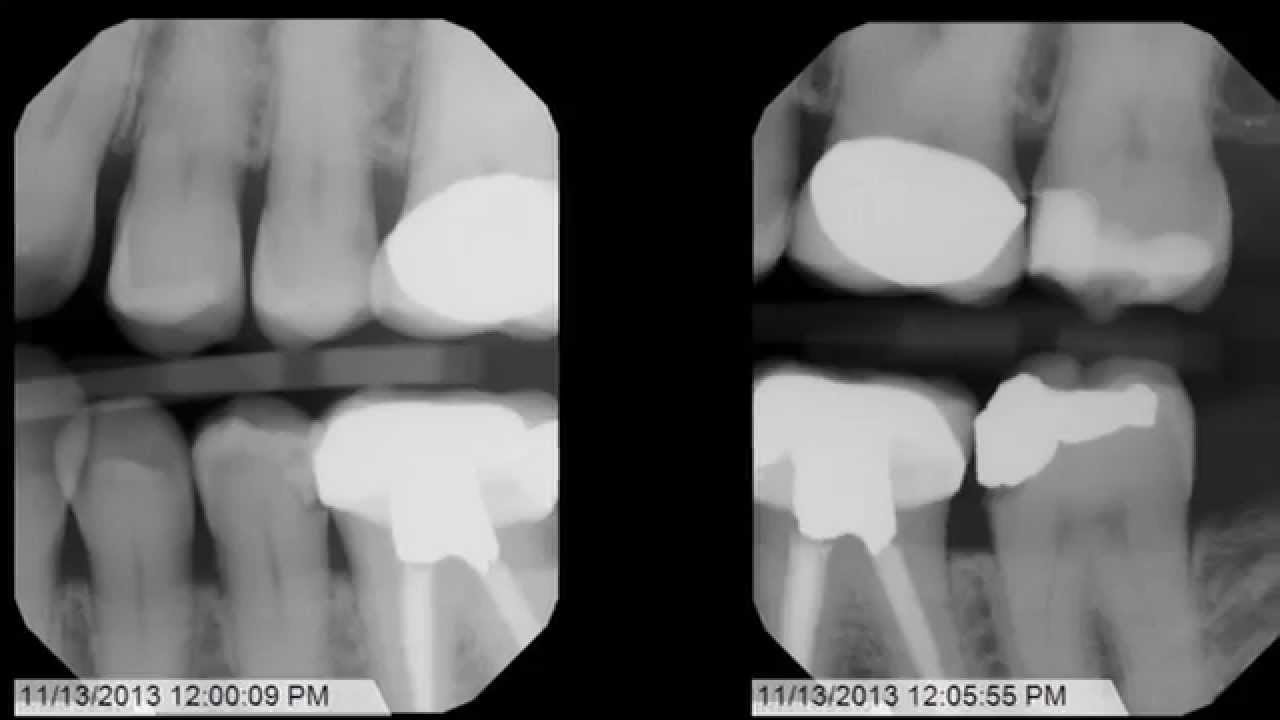

Was interpreted as collimator X-ray source and PID are in Cone cut or partial images are often frustrating to the dental practitioner.

This is uncomfortable for the patient and may produce an inadequate view of the teeth and surrounding bone. The Benefits of a Cone Beam X-Ray. A cone beam takes a 3-D image of your teeth soft tissue nerve pathways and bone with just one scan. The other region of the X-ray is clear with the structures seen clearly. Instead you get x-ray vision. Cone-cut kōnkŭt Manifestation visible in a dental radiograph in which a portion of the image is missing due to the radiation beams having been blocked by improper aim of the cone or position-indicating device qv.

Bitewings show teeth above the gum line and the height of the bone between teeth. The shape of the cone-cut depends on the type of collimator used when exposing the receptor. This angulation is derived from the average vertical angulation of the maxillary and mandibular teeth when in occlusion and allows the x-rays to strike the film at a 90 degree angle providing the most accurate representation of the teeth on the film with maximal overlap of the buccal and lingual alveolar crests and cusps of the teeth. The most common being the image receptor is not in line with the position indicating device PIDradiographic coneHence the collimator which reduces the size and shape or cross-sectional area of the X-ray beam doesnt completely exposes the film resulting in cone cut. Round Cone Cut Rectangular Cone Cut.

Projection errors PID alignment artifact If the PID is misaligned and the x-ray is not centered over the film a partial image is seen on the resultant radiograph this partial image is called cone-cut. The shape of the cone-cut depends on the type of collimator used when exposing the receptor. This results from the x-ray beam not positioned perpendicular over the film. This is uncomfortable for the patient and may produce an inadequate view of the teeth and surrounding bone. Three simple rules serve to identify and correct any errors.

The attenuated x-rays are detected on the opposite side by an x-ray detector which has multiple dexels in the x and y-axis 2. Cone-cut kōnkŭt Manifestation visible in a dental radiograph in which a portion of the image is missing due to the radiation beams having been blocked by improper aim of the cone or position-indicating device qv. A cone beam x-ray can get a more accurate picture than a conventional x-ray. So if you have white space on the mesial aspect. Medical Dictionary for the Dental Professions Farlex 2012 Want to thank TFD for its existence.

The other region of the X-ray is clear with the structures seen clearly. Online ordering offers a number of advantages over traditional phoned or faxed orders. Projection errors PID alignment artifact If the PID is misaligned and the x-ray is not centered over the film a partial image is seen on the resultant radiograph this partial image is called cone-cut. Hence the collimator which reduces the size and shape or cross-sectional area of the X-ray beam doesnt completely exposes the film resulting in cone cut. Cone cut may be caused by.

When using digital imaging the cone-cut appears as an opaque or white area. Receptor instruments with beam guides facilitate beam centering over the receptor when properly assembled. If you cut the target off at the edge of the beam cone cut simply move the beam over toward the area of cone cut. Cone cut errors are caused by not centering the x-ray beam over the receptor. PDF In routine dental radiography one may encounter numerous radiographic errors one of which may be partial images or cone cuts.

The attenuated x-rays are detected on the opposite side by an x-ray detector which has multiple dexels in the x and y-axis 2. PDF In routine dental radiography one may encounter numerous radiographic errors one of which may be partial images or cone cuts. A cone beam takes a 3-D image of your teeth soft tissue nerve pathways and bone with just one scan. Cone cut appearance Cone cut appearance refers to a clear unexposed area in a dental radiograph. Phalangioma The term phalangioma was used by Dr.

Cone cut may be caused by various reasons. It can be. Dental x-rays are taken with you sitting upright in a chair. Cone-cuts appear as a clear zone on traditional radiographs after processing due to the lack of x-ray exposure in the area of the cut. Instead you get x-ray vision.